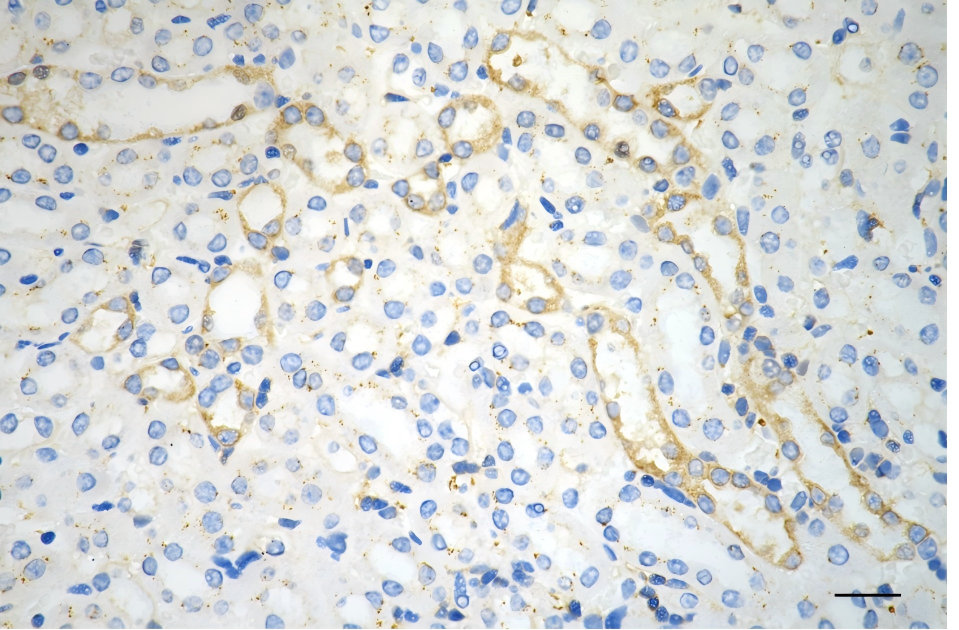

Immunohistochemistry was performed on paraffin-embedded human glioblastoma using PKC alpha antibody. Antigen retrieval was done in sodium citrate buffer (pH 6.0). DAB was used for detection, with hematoxylin counterstaining. Images were acquired using a Nikon Ci-L Plus microscope (40× objective). Scale bar: 25 μm.

-

Immunohistochemistry was performed on paraffin-embedded mouse brain using PKC alpha antibody. Antigen retrieval was done in sodium citrate buffer (pH 6.0). DAB was used for detection, with hematoxylin counterstaining. Images were acquired using a Nikon Ci-L Plus microscope (40× objective). Scale bar: 25 μm.

Immunohistochemistry was performed on paraffin-embedded mouse kidney using PKC alpha antibody. Antigen retrieval was done in sodium citrate buffer (pH 6.0). DAB was used for detection, with hematoxylin counterstaining. Images were acquired using a Nikon Ci-L Plus microscope (40× objective). Scale bar: 25 μm.